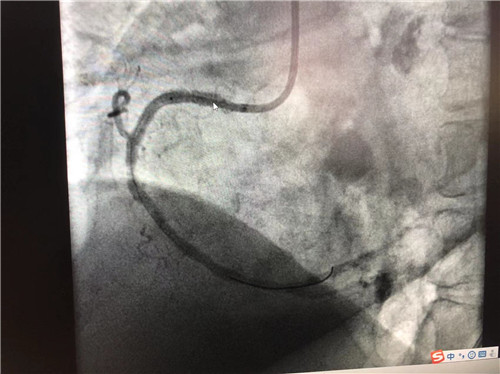

時間就是心肌,時間就是生命。導管室內(nèi),心血管內(nèi)科副主任徐先進、主任助理農(nóng)彥林已然待命,病人一到,團隊立即為其行深靜脈穿刺泵入血管活性藥物等,情況緩解后,行多體位冠狀動脈造影,確認RCA(右冠狀動脈)近端完全閉塞。經(jīng)家屬同意,在汪念東院長的指導下,徐先進、農(nóng)彥林、張星為患者行經(jīng)皮冠狀動脈球囊擴張成形術(shù)+經(jīng)外周靜脈穿刺中心靜脈置管術(shù)。術(shù)中,張奶奶再次出現(xiàn)室顫,心血管內(nèi)科團隊臨危不亂,立即予以300焦電除顫搶救,患者竇性心律恢復。隨后,球囊擴張為其置入心臟支架,復查造影顯示血管恢復暢通,無明顯夾層,殘余狹窄不到10%。術(shù)后,張奶奶血壓偏低,轉(zhuǎn)入ICU無創(chuàng)呼吸監(jiān)護,2天后轉(zhuǎn)回心血管內(nèi)科護理。

術(shù)后